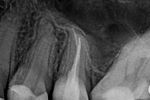

Revisionsbehandlung eines Unterkiefermolaren (37) vor geplanter Überkronung (Dr. Maik Göbbels) Download